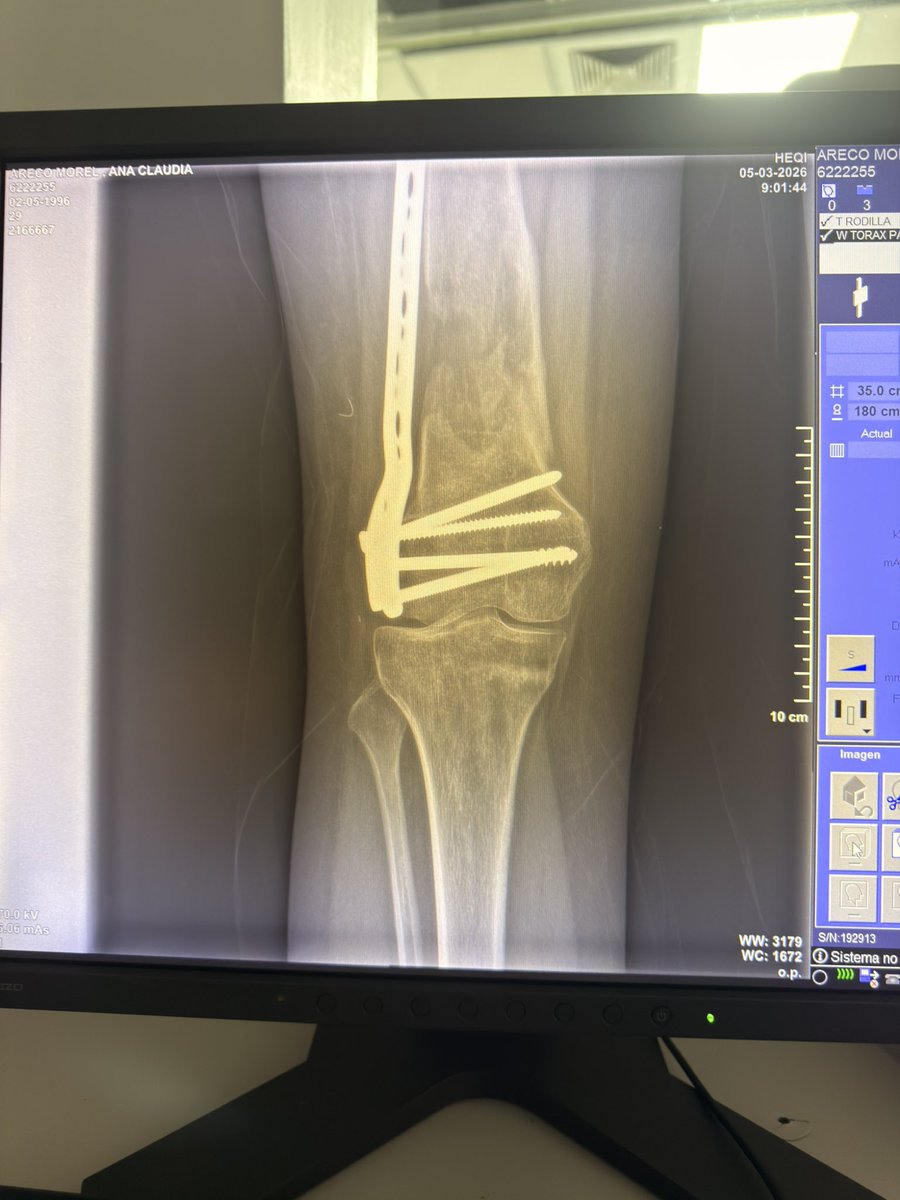

Essas sao as minhas radiografias, da pra ver o meu nome. Como o joelho nao esta dobrando (ja foram 5 cirurgias) eu nao consigo dirigir e ir com frequência nos correios e por isso uma menina se dispôs a fazer uma CEG de todas as minhas coisas ✨🩵 Estarei passando o contato dela.